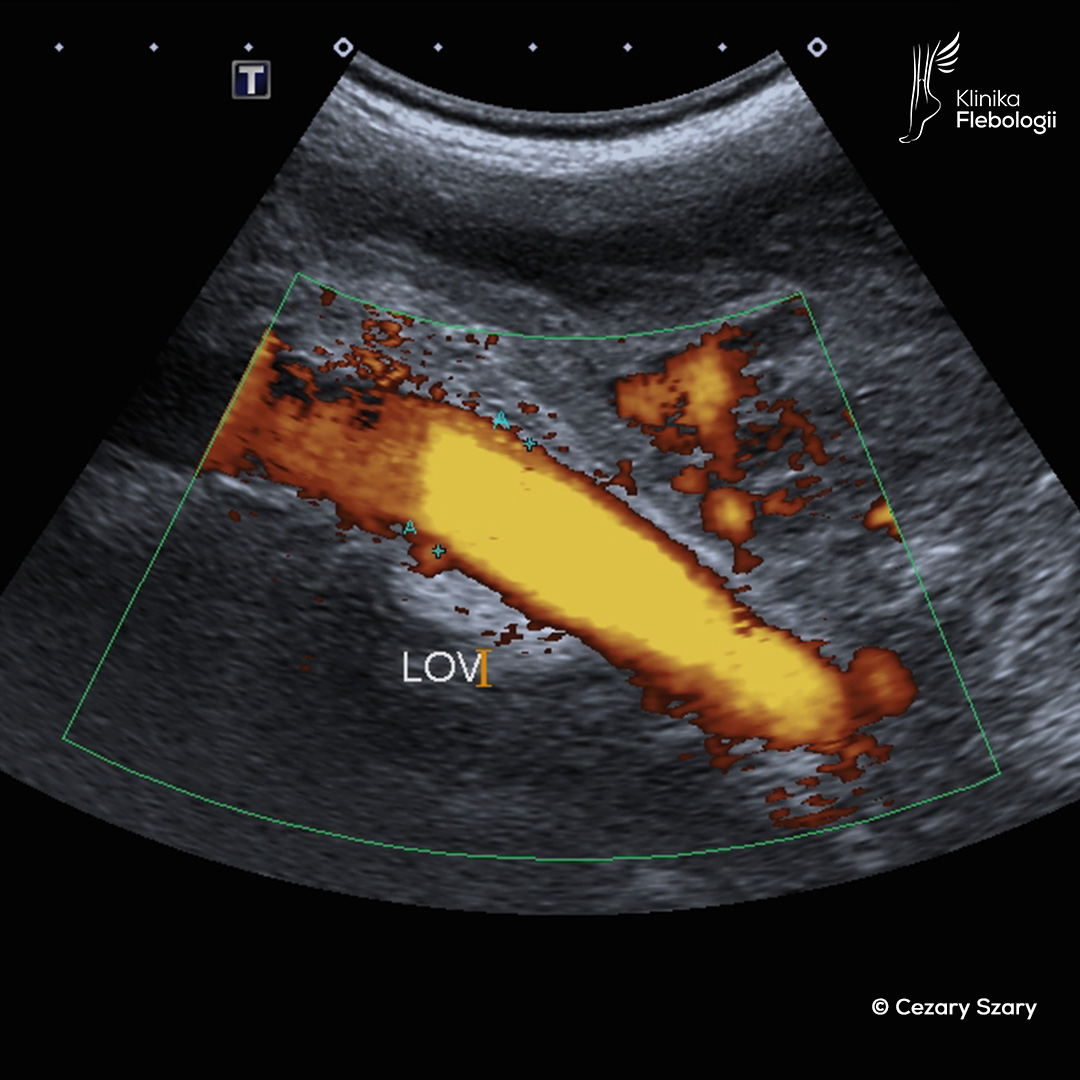

Dziś sytuacja wygląda zupełnie inaczej. Ultrasonografia dopplerowska (USG Doppler) stała się złotym standardem w diagnostyce żylnej – to nasze podstawowe narzędzie, które pozwala precyzyjnie ocenić stan Twoich żył przed rozpoczęciem jakiegokolwiek leczenia. Dzięki zaawansowanej diagnostyce obrazowej możemy nie tylko dokładnie zaplanować terapię, ale też sprawdzić jej skuteczność.

W przypadkach wymagających bardziej szczegółowej diagnostyki (tzw. diagnostyki rozszerzonej układu żylnego), stosuje się zaawansowane techniki obrazowania, takie jak: wenografia rezonansu magnetycznego (skrót ang. MRV) czy wenografia tomografii komputerowej (skrót ang. CTV). Ultrasonografia wewnątrznaczyniowa (skrót ang. IVUS) oraz flebografia cyfrowa są raczej metodami, po które sięgamy już w czasie wykonywania zabiegów naprawczych na układzie żylnym.